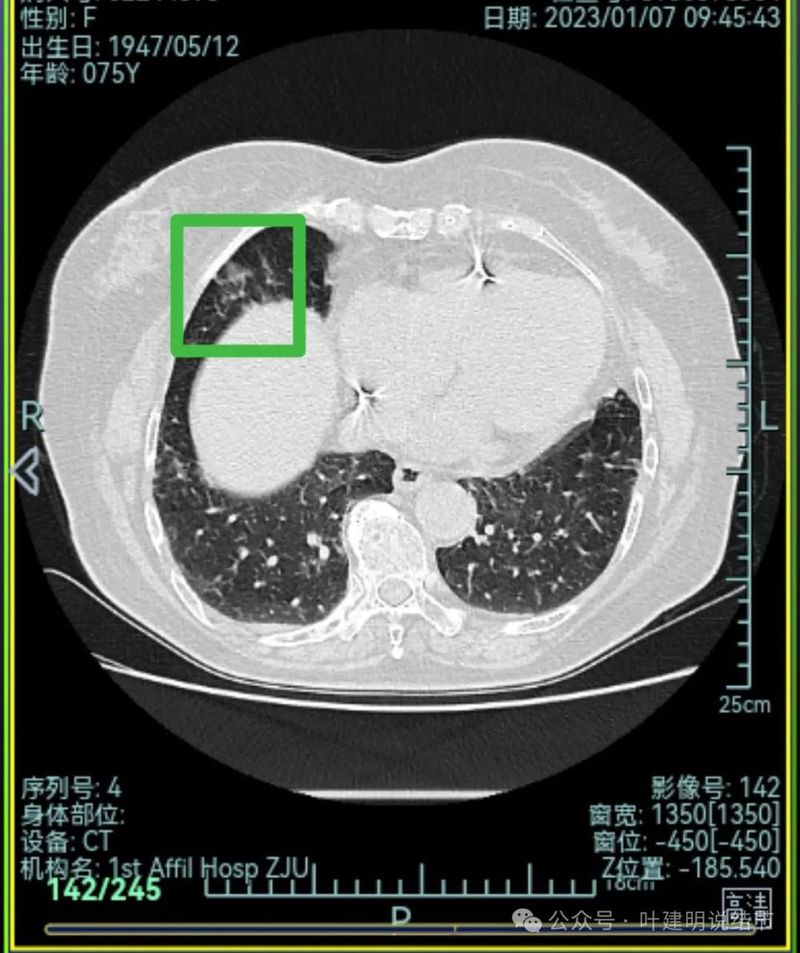

先来看2023年1月时的影像:

右上叶混合密度病灶,有毛刺征,轮廓较清,单次单处看是要考虑恶性的;左上叶磨玻璃结节,轮廓较清,密度较淡,瘤肺边界部分边缘稍不清。

右上叶混合密度结节了,瘤肺边界欠清,周围有晕;左上叶磨玻璃结节,有毛刺征,整体轮廓较清,瘤肺边界略显糊。

右上叶混合密度结节,有分叶征,内部密度杂乱,有毛刺征,灶内有空泡征,单处单灶看也是与恶性较为符合;左上叶两处磨玻璃阴影,轮廓稍糊,边界稍不清,感染稍倾向炎性些。

当时影像考虑:

从上述两肺多发病灶来看,虽有多处也恶性的混合密度结节也是符合的,但由于病灶太多,有的轮廓与边界模糊,首次发现肯定要先考虑感染性病变,并依病毒感染予以治疗并适时复查。因为退一步讲,即使多原发肺癌是这个样子,近80岁的高龄,也肯定不能先考虑手术来解决,那是切不光的。